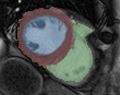

- EMSegment-CardioA1seg.jpg 1,124 × 940; 70 KB